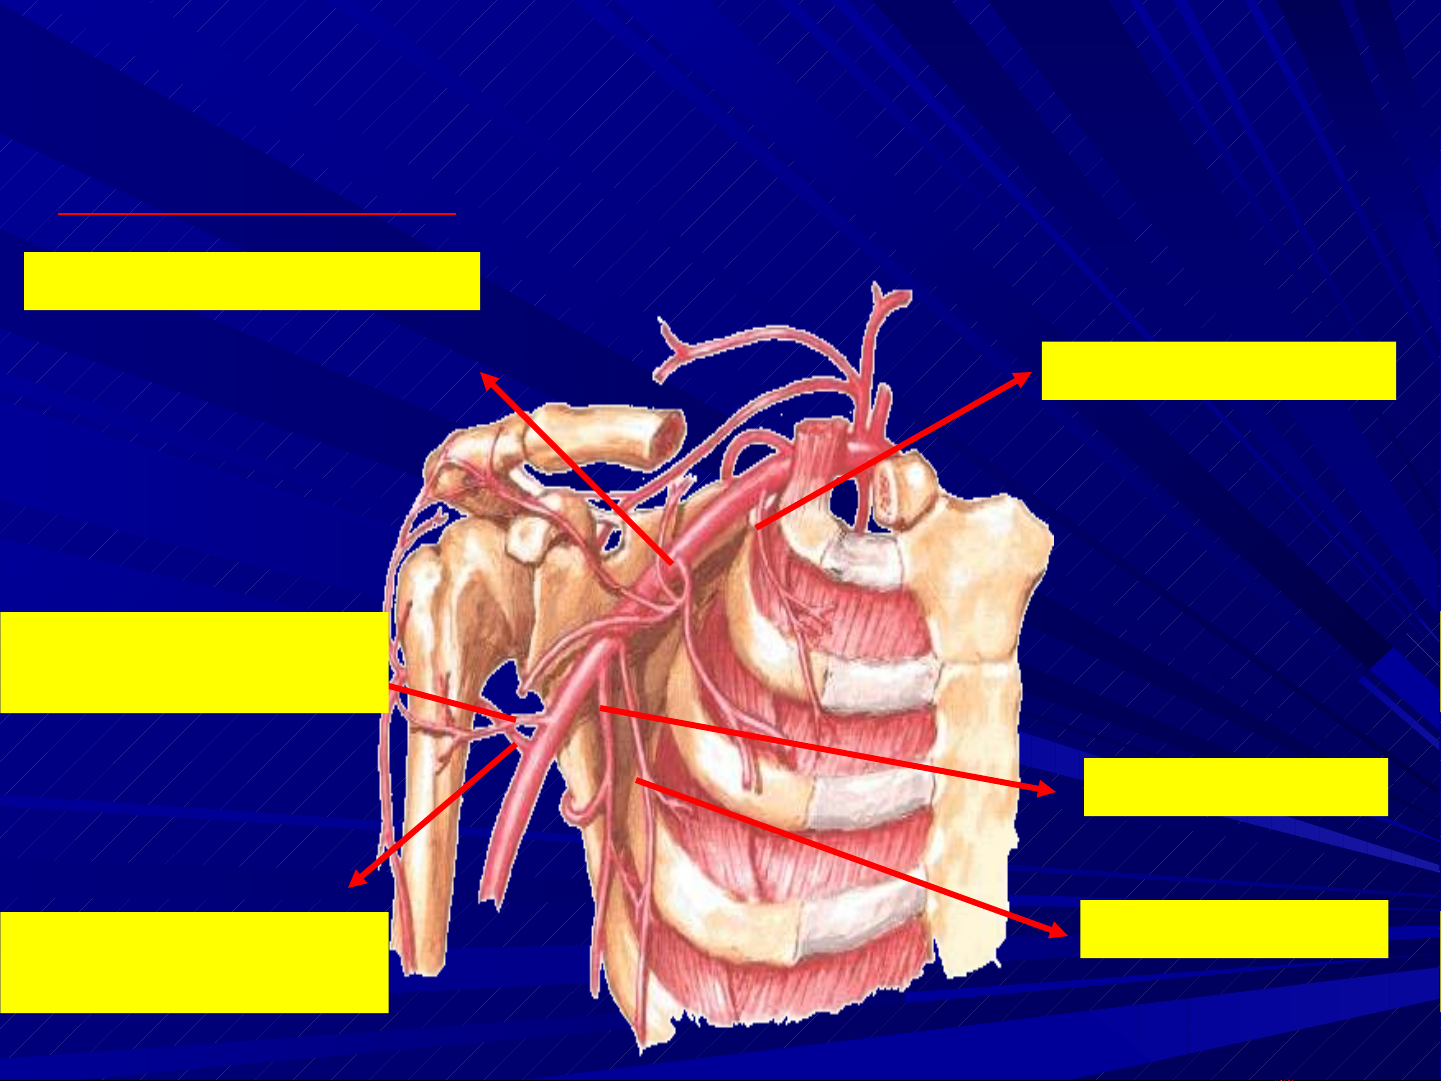

1- Đ NG M CH NÁCH:Ộ Ạ

1- ĐM NG C TRÊNỰ

2- ĐM CÙNG VAI NG CỰ

3- NG C NGOÀIỰ

4- ĐM D I VAIƯỚ

5- ĐM MŨ CÁNH TAY

TR CƯỚ

6- ĐM MŨ CÁNH TAY

SAU

NHÁNH ĐÒN

NHÁNH CÙNG VAI

NHÁNH DELTA

NHÁNH NG CỰ